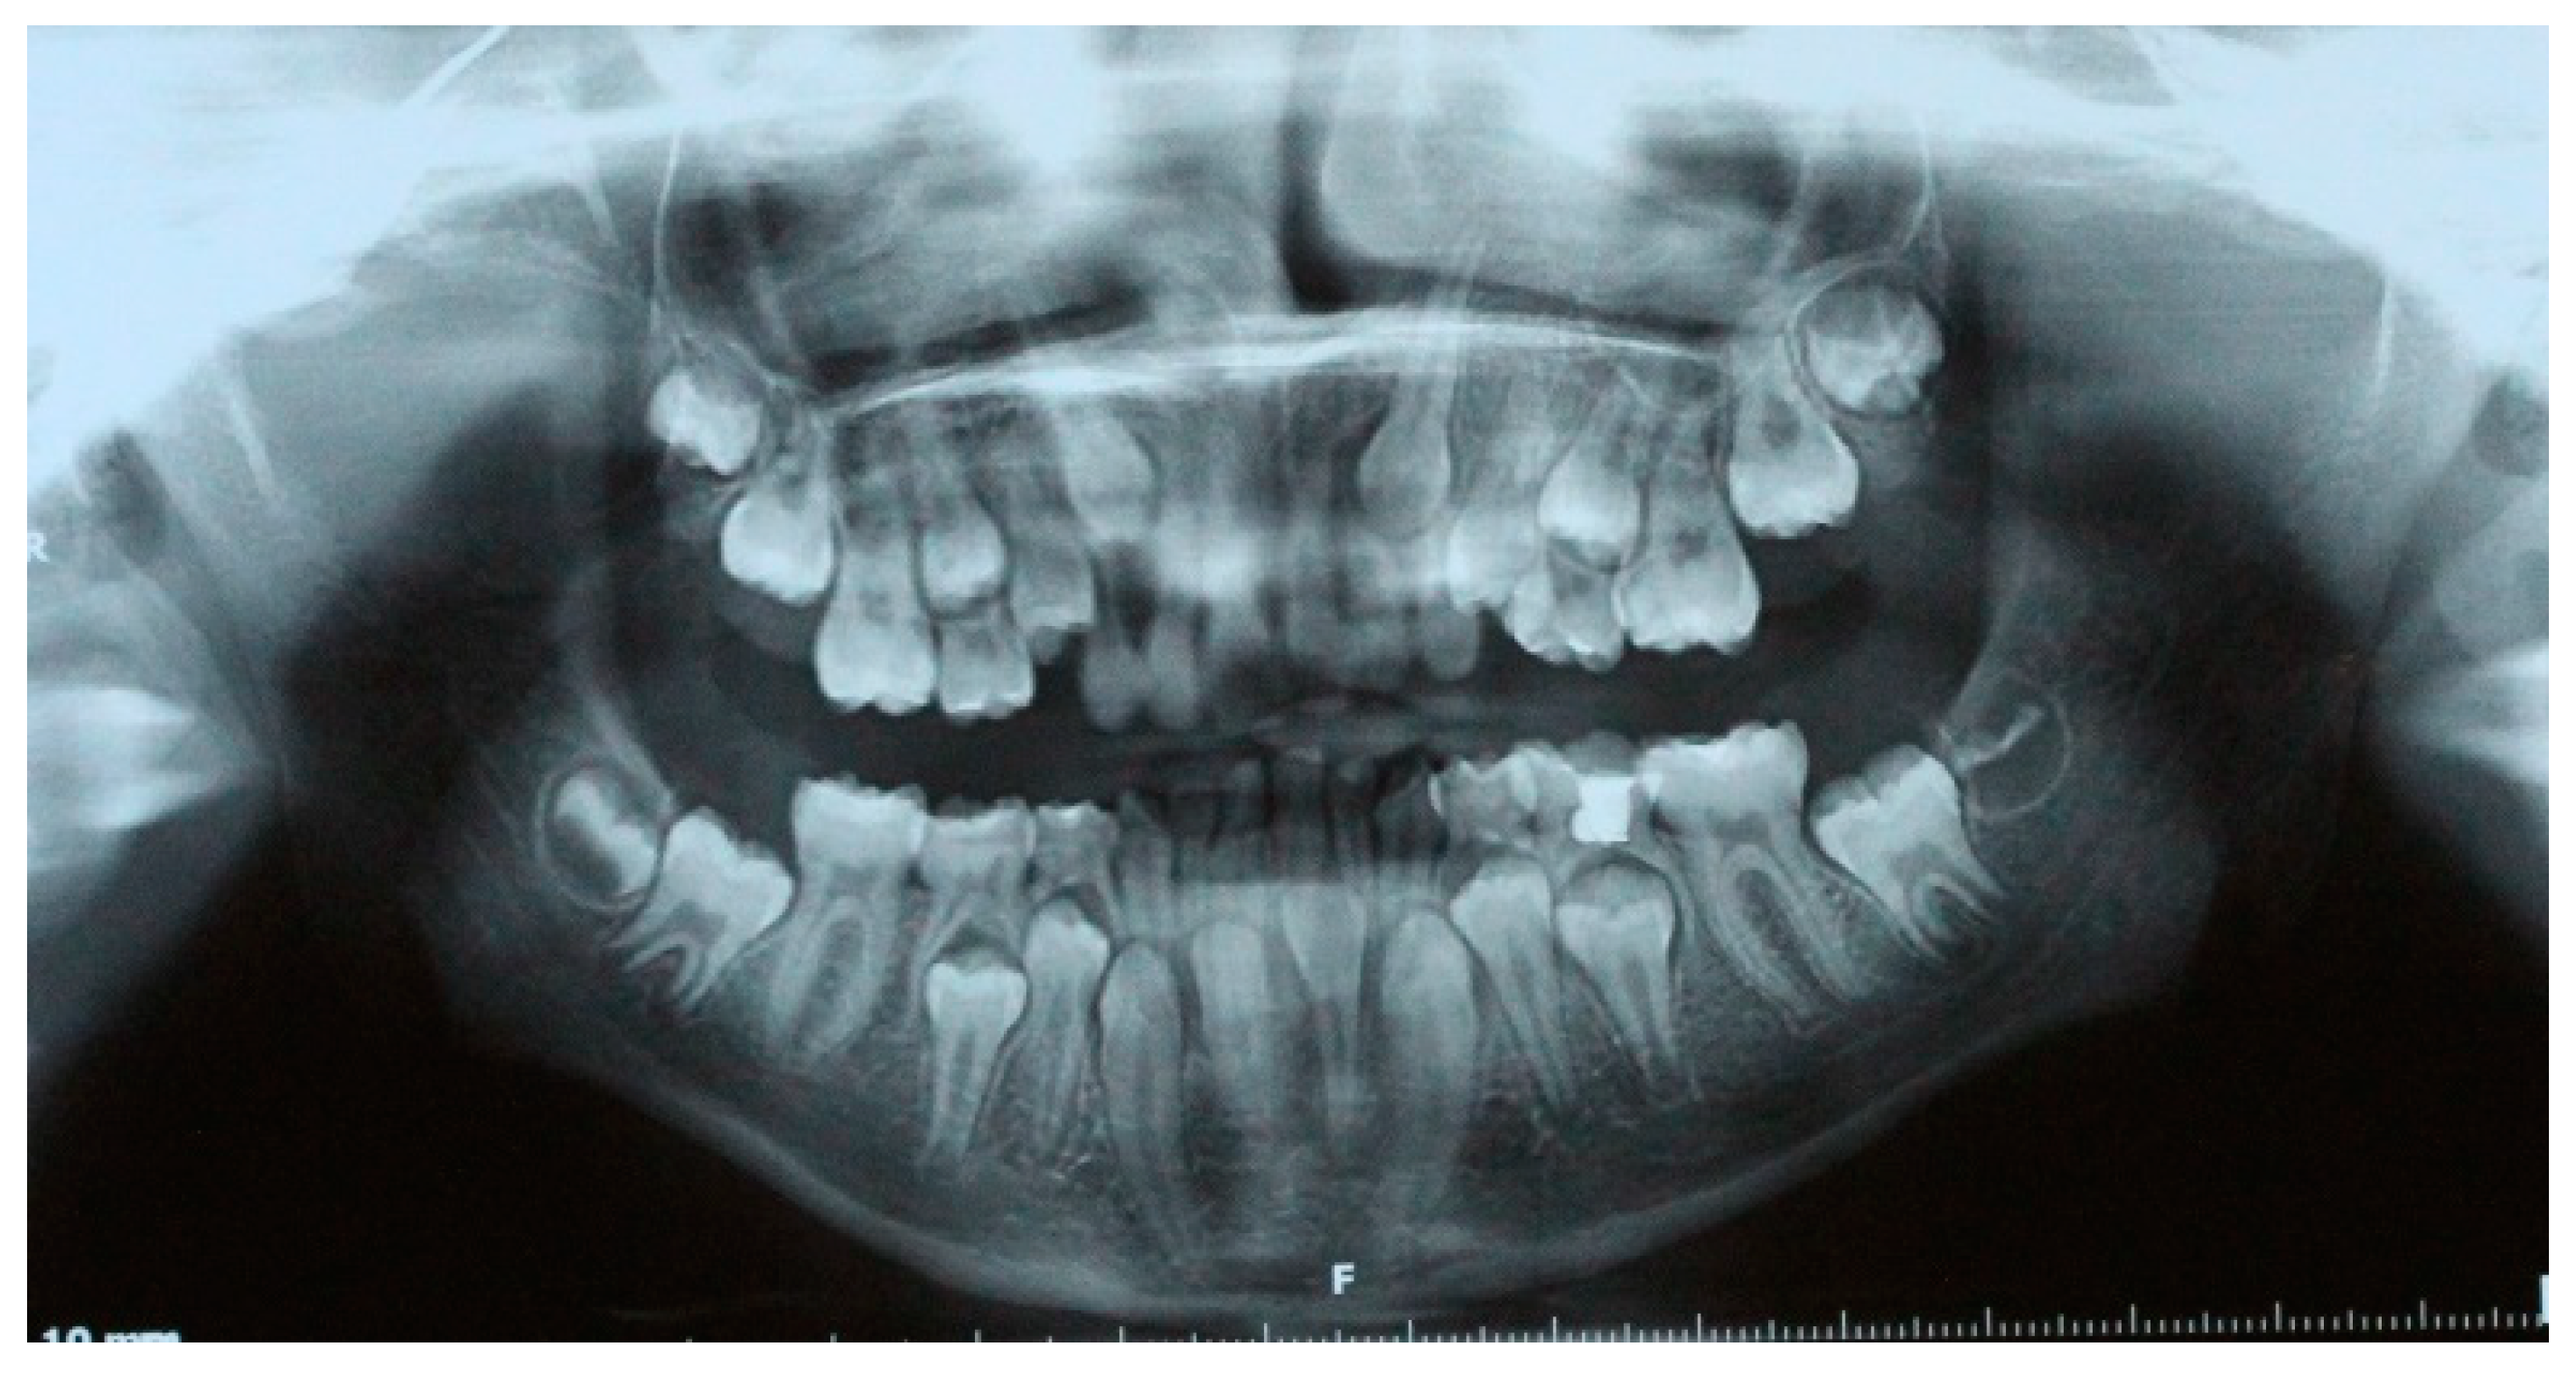

An 11-year-old female patient presented with a Class II molar relationship and a Class II skeletal relationship due to downward and backward rotation of the mandible. Increased overjet (21–71) was recorded, and deciduous lower central incisors and canines were in place while in the upper arch incisors had normally erupted. Upper canines had not been erupted yet and deciduous molars were in place in the lower arch. Radiographic examination with panoramic and lateral cephalometric X-ray in the beginning (Figure 1) revealed that lower central incisors were congenitally missing, and later incisors and canines had their root almost fully formatted. The medical records that were provided indicated that right after birth the newborn was admitted to the neonatal intensive care unit for a cleft of the soft palate and a significant lower jaw retrognathism. Initial cytogenetic report was normal and the check for pathologic findings on chromosome 22, which possibly applies to Di George syndrome (22q11.2 region), was negative. No other local or systemic factors were identified. The cleft was surgically treated at the 15th month of age. The case was characterized as presenting delayed tooth eruption alongside the skeletal and dental Class II relationship.

Figure 1. Initial panoramic (a) and lateral cephalometric X-ray (b) and tracing (c).